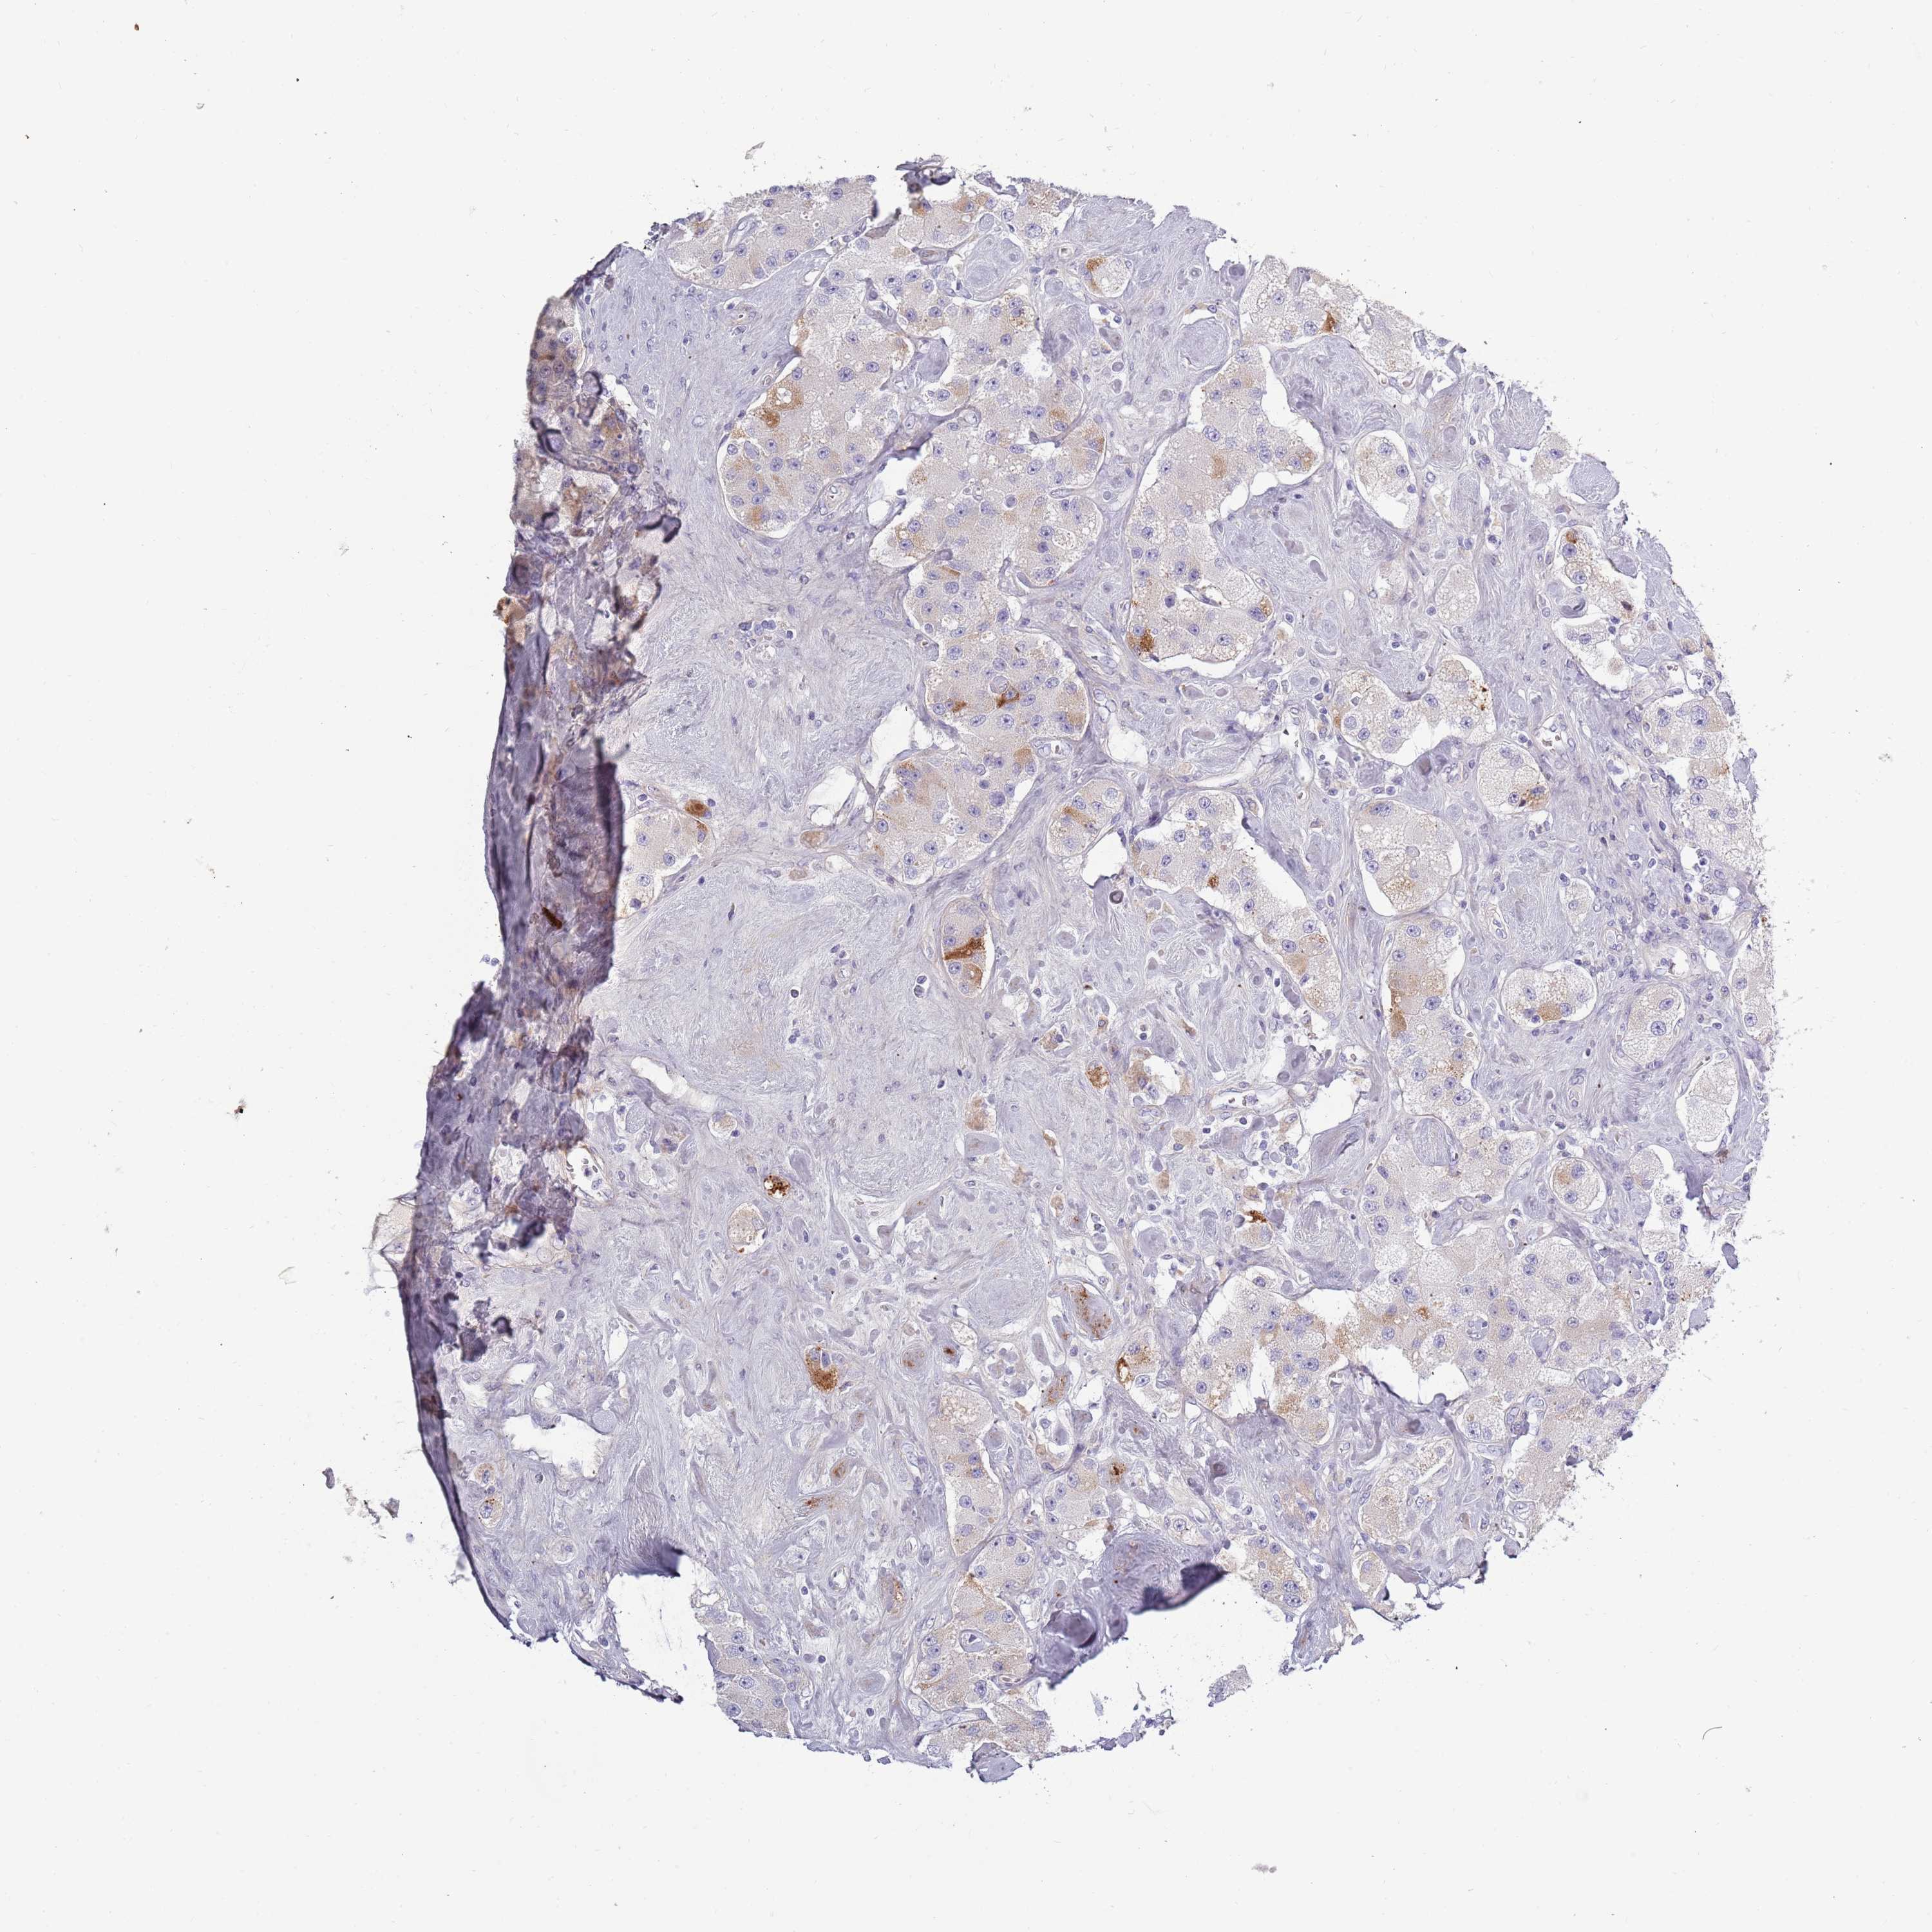

CARCINOID - Protein expressioni

A mouse-over function shows sample information and annotation data. Click on an image to view it in a full screen mode. Samples can be filtered based on level of antibody staining by selecting one or several of the following categories: high, medium, low and not detected. The assay and annotation is described here.

Antibody stainingi

Antibody staining in the annotated cell types in the current human tissue is reported as not detected, low, medium, or high, based on conventional immunohistochemistry profiling in selected tissues. This score is based on the combination of the staining intensity and fraction of stained cells.

Each image is clickable and will lead to virtual microscopy that enables deeper exploration of all samples and also displays staining intensity scores, fraction scores and subcellular localization as well as patient and tissue information for each sample.

Antibody HPA047154

Staining

High

Medium

Low

Not detected

Intensity

Strong

Moderate

Weak

Negative

Quantity

>75%

75%-25%

<25%

None

Location

Nuclear

Cytoplasmic/membranous

Cytoplasmic/membranous,nuclear

Carcinoid, malignant, NOS

Carcinoma, NOS